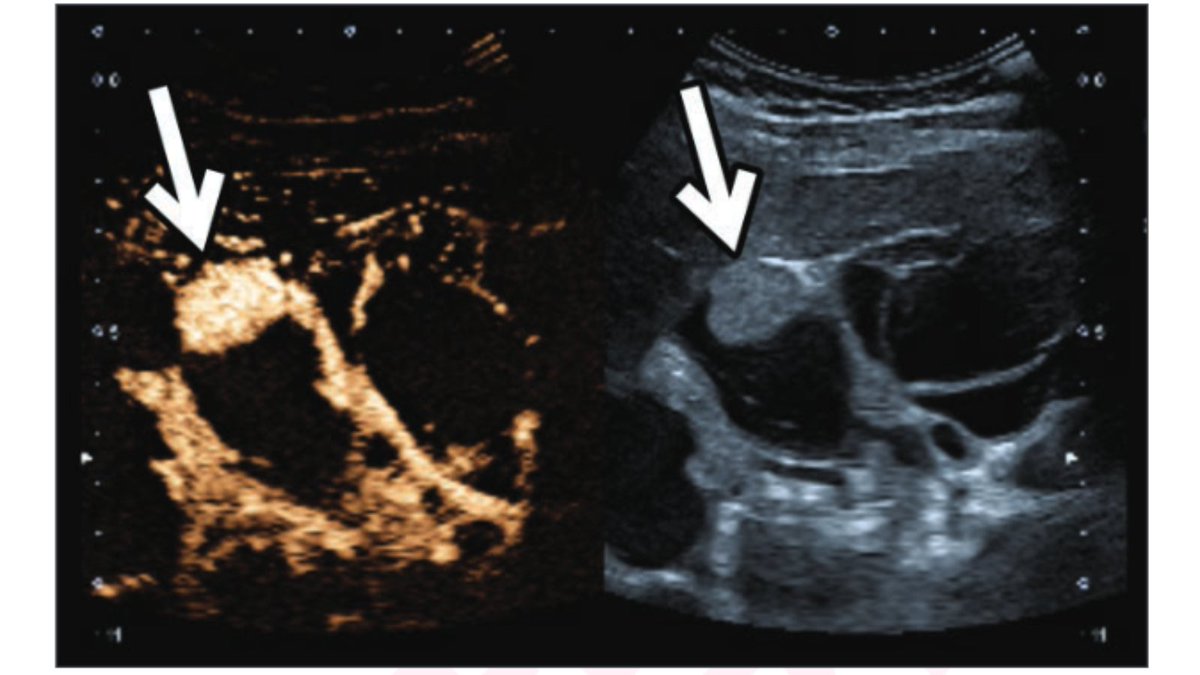

New AJR Accepted Manuscript: "Contrast-Enhanced Ultrasound of the Indeterminate Renal Mass, From the AJR 'How We Do It' Special Series" By Drs Elbanna, Atri, & team UofT Medical Imaging ajronline.org/doi/10.2214/AJ…

New <a href="/AJR_Radiology/">AJR</a> Accepted Manuscript:

"Contrast-Enhanced Ultrasound of the Indeterminate Renal Mass, From the AJR 'How We Do It' Special Series"

By Drs Elbanna, Atri, &amp; team <a href="/UofTMedIm/">UofT Medical Imaging</a>

ajronline.org/doi/10.2214/AJ…